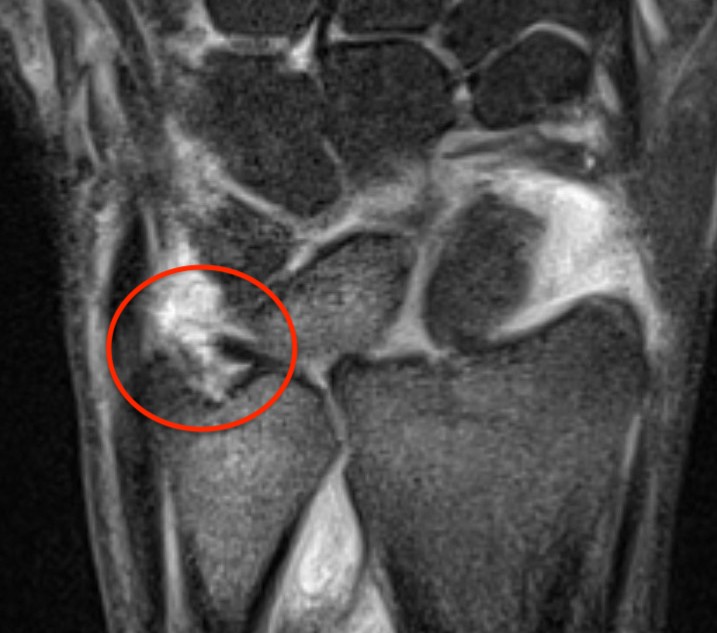

Class 2 Degenerative TFCC tears

Central TFCC tear with ulna positive variance an ulnocarpal abutment on MRI

Background

Ulna impaction syndrome / Ulno-carpal abutment

Progression of wear

- TFCC thinning

- ulna head and lunate cartilage wear

- TFCC perforation

- lunate-triquetral ligament injury

- ulnocarpal osteoarthritis

Usually associated with ulna positive variance and treated with ulna shortening